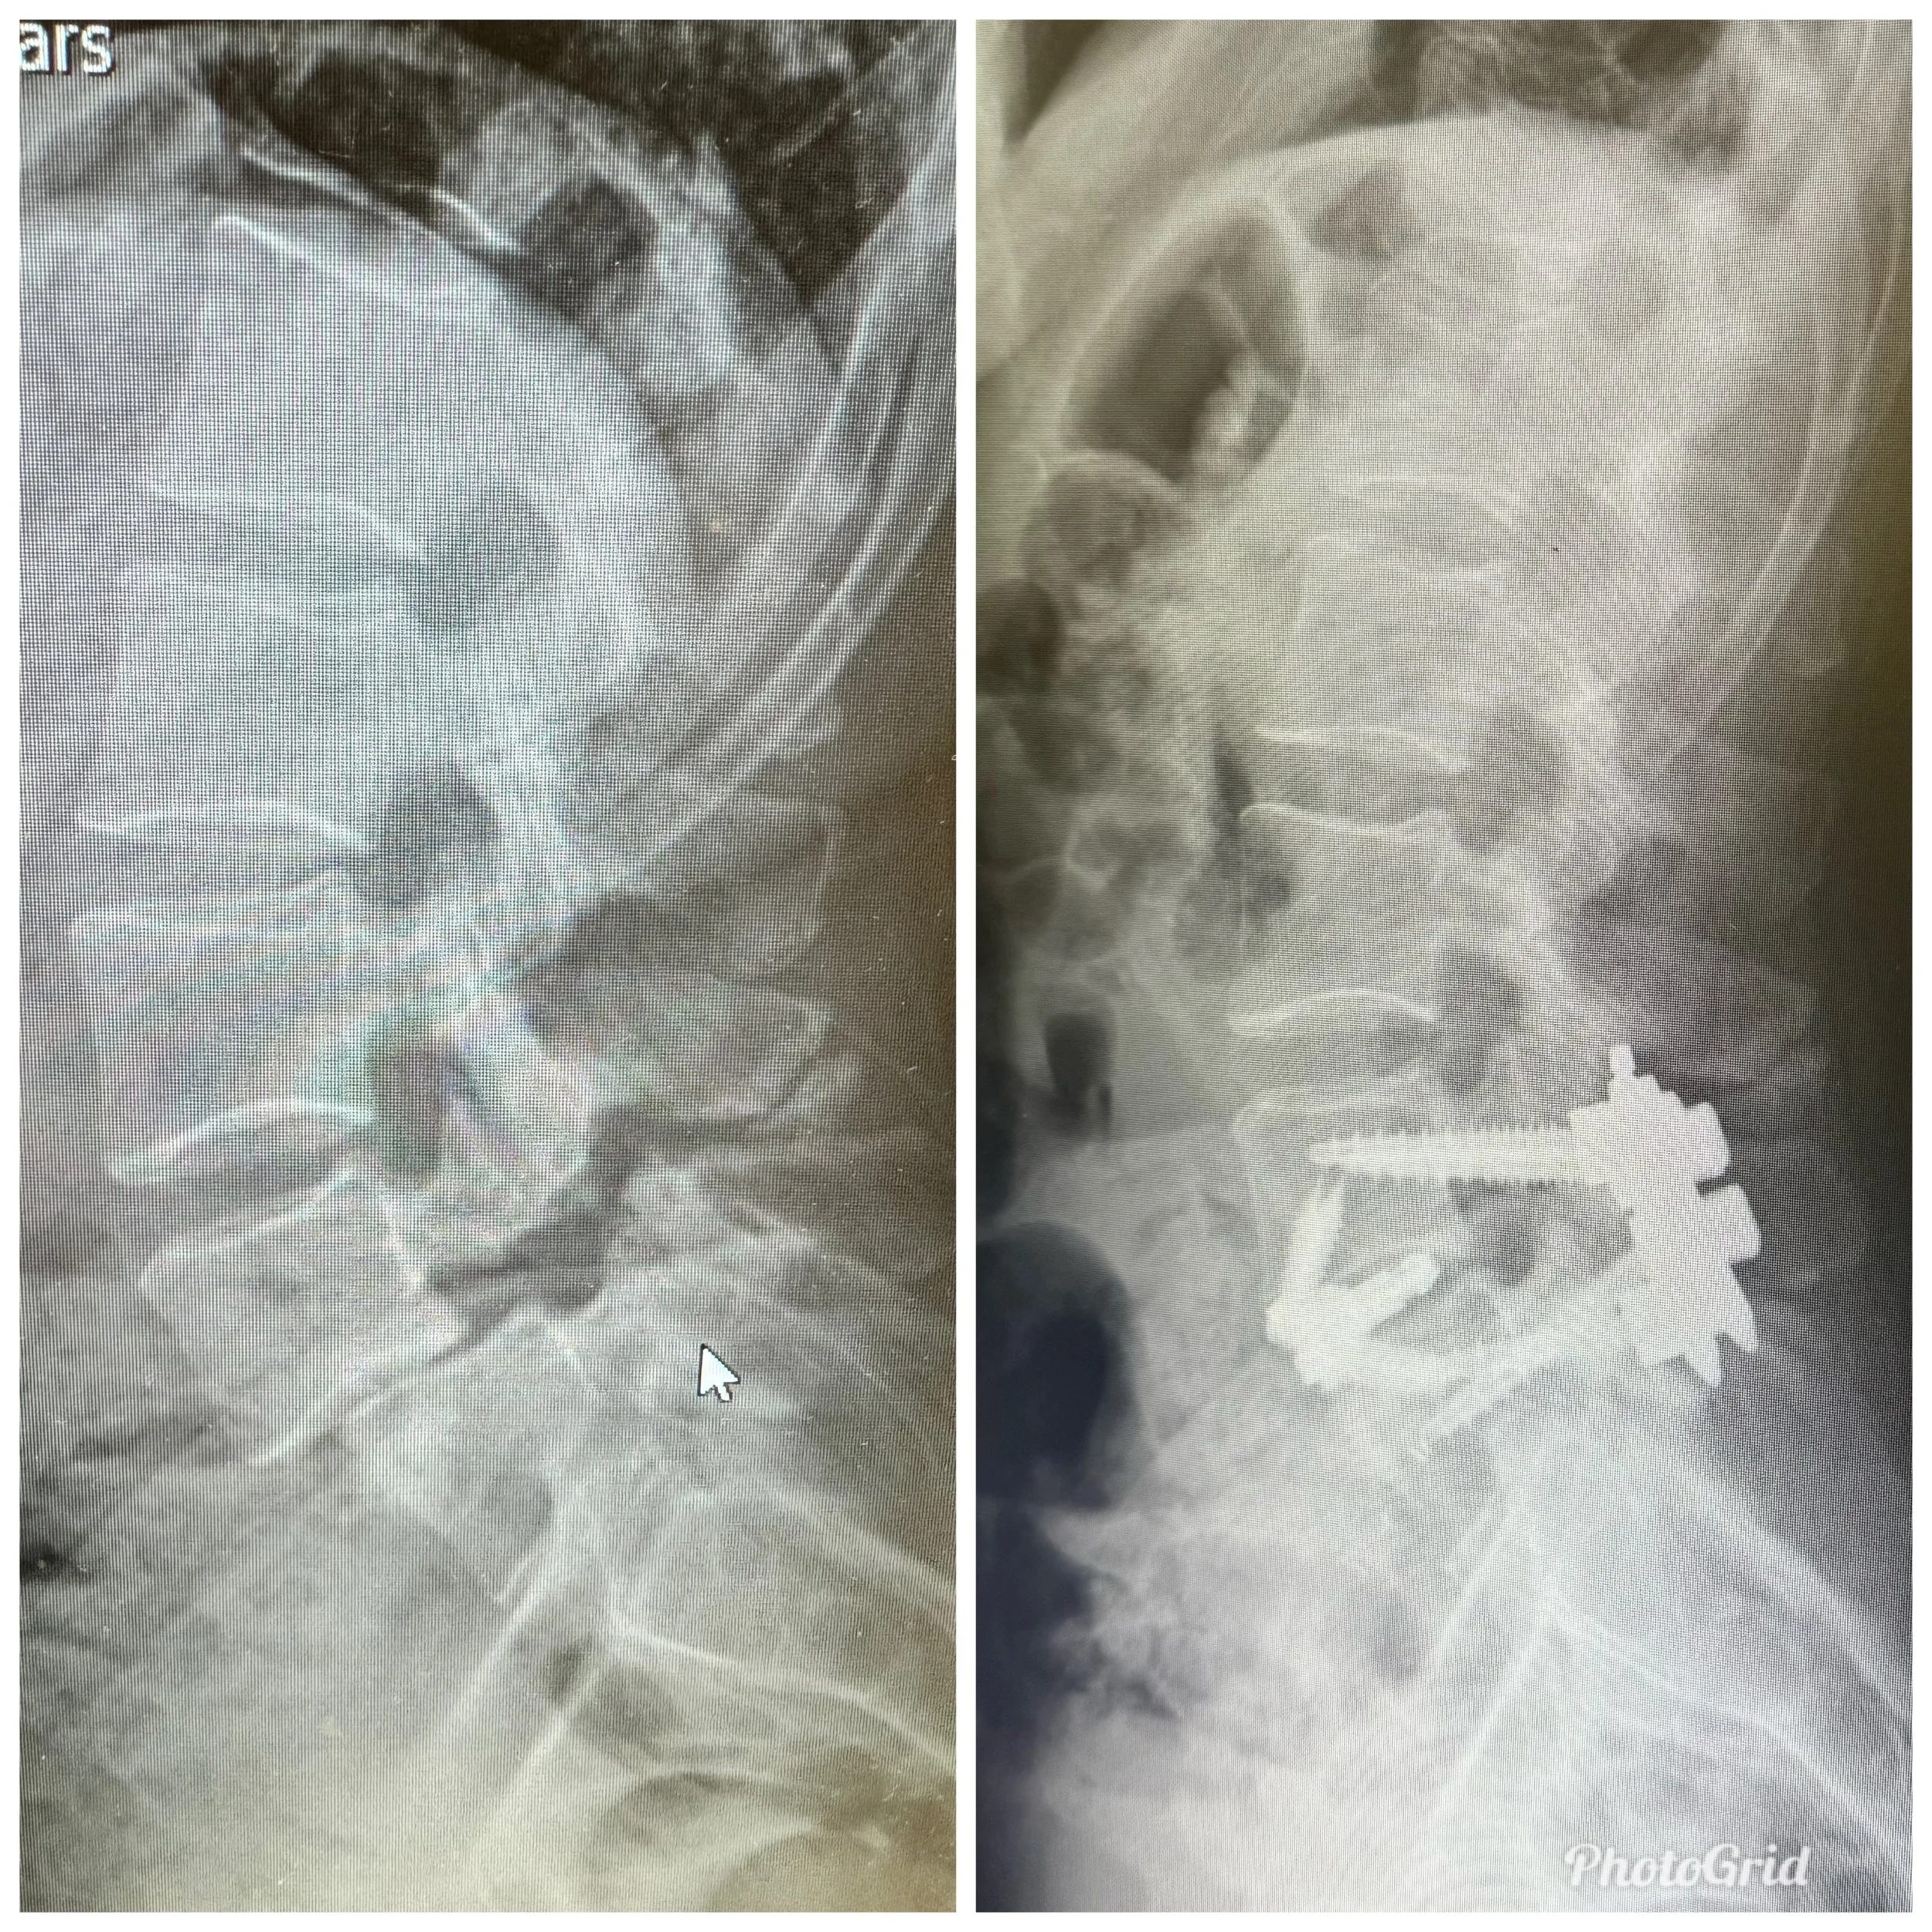

6 Days Post Op Update

I have 8 titanium screws, a titanium cage with bone graft and 2 rods